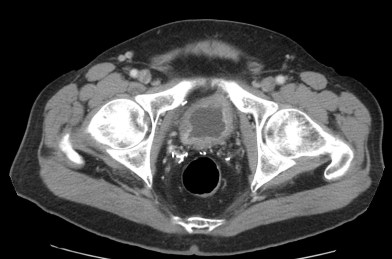

CASO CLÍNICO: Recopilatoción.

Paciente de 59 años con antecedentes personales de Cá de vejiga.

Se le realiza una Uro-Tc por seguimiento al año, aunque en esta ocasión el paciente refiere episodio de hematuria.

Tras el tratamiento de la recidiva y nefrostomía para la hidroureteronefrosis, vuelve acudir al hospital a los 9 meses por episodio de dolor en FD y malestar general. Se realiza una ecografía de urgencias.

Se realiza nueva TC bifásico abdominopélvio y Uro TC.

- Paciente con numerosas recidivas por Cá vejiga.

- Ha desarrollado un tumor metacrónico en pelvis renal derecha, también responsable de la hidroureteronefrosis.

- Mala evolución radiológica del proceso a expensas de metástasis pulmonares y hepáticas.